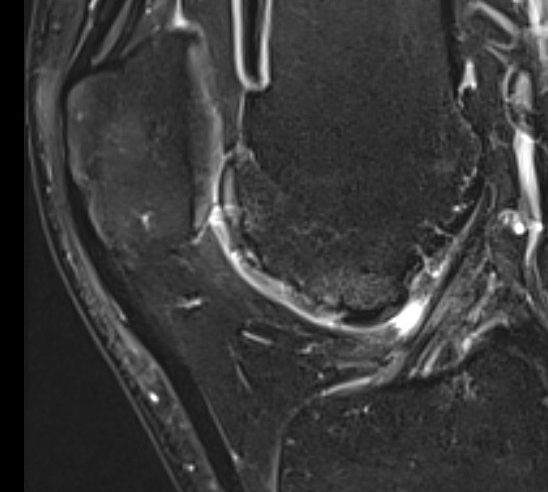

MRI